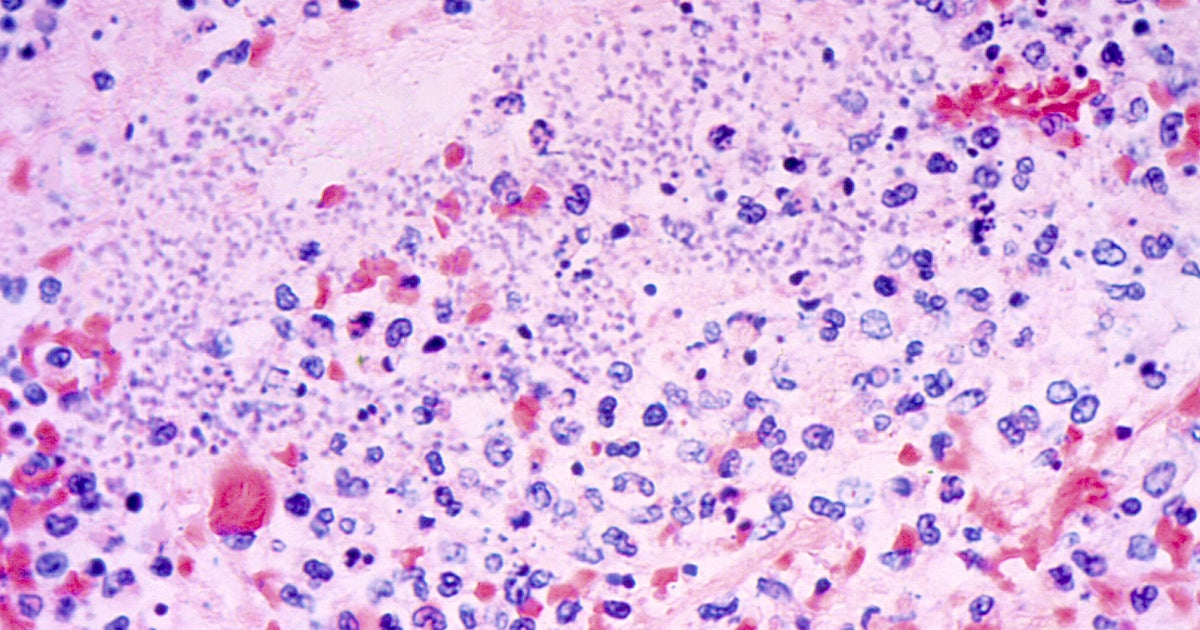

Plague is rare to humans, with on average about seven cases reported annually in the U.S., most of them in the western states, according to federal health of… [1961 chars]